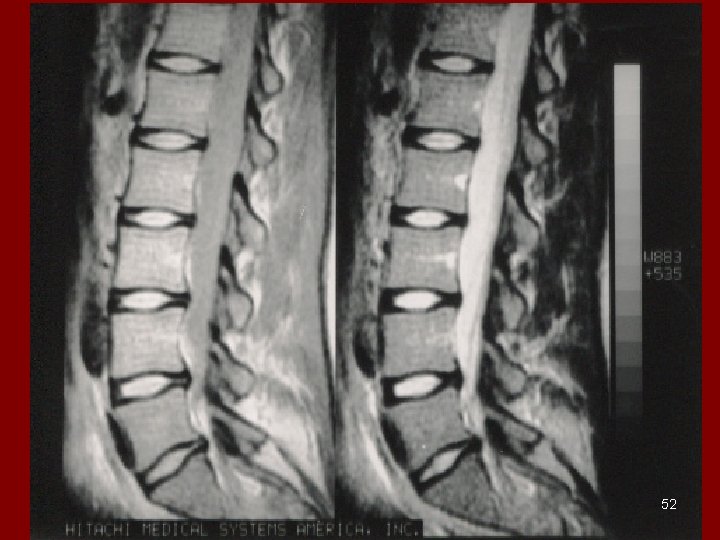

MRI • NOT IONIZING RADIATION • USES MAGENTIC RESONANCE • (RADIO WAVES) • Jane Schultz, R. T. (MR) 51

52

RADIOGRAPHY VS MRI BONE vs. Soft Tissue 55